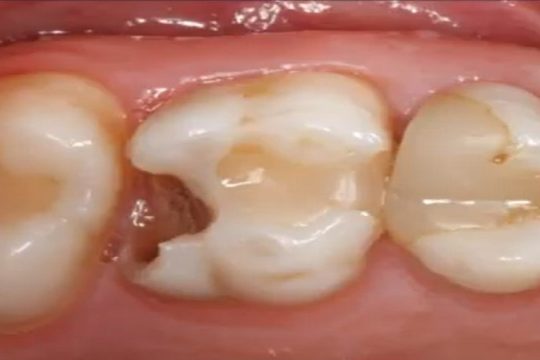

Presented by the Department of Pediatric Dentistry (Ghent University), in the context of 10 years’ experience with Biode...